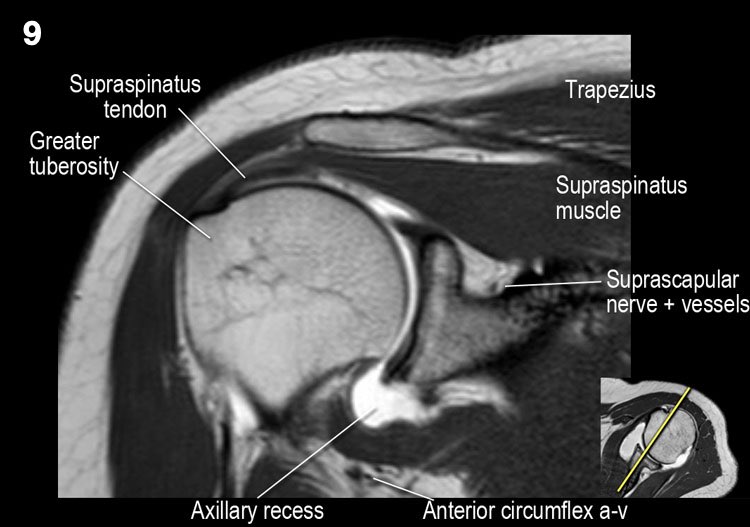

Giải phẫu mặt cắt vành và danh sách kiểm tra

- Lưu ý dây chằng quạ-mỏm cùng vai.

- Lưu ý thần kinh và mạch máu trên vai.

- Tìm kiếm hội chứng chèn ép cơ trên gai do gai xương khớp cùng-đòn hoặc dây chằng quạ-mỏm cùng vai dày lên.

- Tìm kiếm tràn dịch quá mức trong túi hoạt dịch dưới mỏm cùng vai và rách gân cơ trên gai.

- Tìm kiếm rách kiểu “rim-rent” của gân cơ trên gai tại chỗ bám của các thớ sợi trước.

- Đánh giá chỗ bám của dây chằng ổ chảo-cánh tay dưới (IGHL) vào xương cánh tay. Đánh giá phức hợp sụn viền-dây chằng phần dưới. Tìm kiếm tổn thương HAGL (bong điểm bám dây chằng ổ chảo-cánh tay tại xương cánh tay).

- Tìm kiếm rách gân cơ dưới gai.

- Lưu ý tổn thương Hill-Sachs nhỏ.

- Tìm kiếm rách gân cơ trên gai.